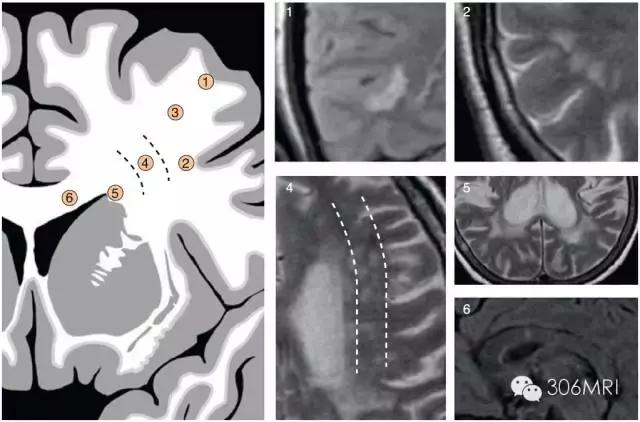

大脑微循环:(A)动脉微循环。1:皮层动脉;2:软脑膜动脉;2.1:短分支 (软脑膜动脉及其短分支对皮层下U型纤维双重供血);3:室管膜下动脉;4:室管膜下穿支动脉;5:豆纹及丘脑穿支动脉;6:跨脑动脉。(B) 静脉微循环。1:皮层静脉;2:表浅髓质静脉;3:室管膜下静脉;4:深部髓质静脉

对于白质区内斑点灶的识别与临床意义所在,有国外学者将白质区域及常见的斑点影像通过画图方式进行了归纳与展示,看到这些,我的膝盖碎了!

部位: ①皮质旁; ②皮层下U型纤维; ③皮层深部非边缘区; ④皮层下边缘区; ⑤脑室旁; ⑥胼胝体。

主要累及皮层旁①/或者胼胝体⑥提示是非血管性模式,其余部位趋于血管性模式或者非特异性模式,提示小血管病因。脑室周围病变取决于病变形状而可能提示血管性模式或者血管周围模式。

常见斑点影形状及发生部位与意义

血管性模式提示为微血管病灶,多指小动脉闭塞;血管周围模式主要提示脱髓鞘病变,如多发性硬化(MS);非特异性模式提示小血管病可能。

将斑点形状与部位归纳入三种不同的基本模式,其意义分别表示:血管性模式-多由小动脉病变引起,最普遍;血管周围模式-血管周围感染性病变引起,是相比少见的病因。典型者是多发性硬化MS,小静脉周围自身免疫性感染引起脱髓鞘;非特异性模式-多由小血管疾病引起。